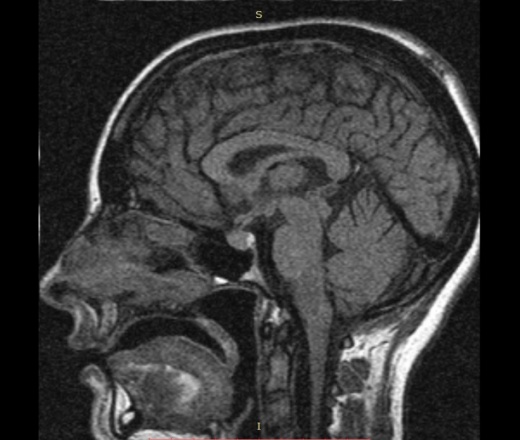

Пациентка девушка 25 лет, направлена для исключения аденомы гипофиза. В течении 6 месяцев отсутствуют менструации. Повышен ФСГ, ЛГ. Родов, травм в анамнезе не было. ВСД по гипотоническому типу, периодические головные боли.

Смущает зона между адено- и нейрогипофизом, которая по Т1, FS практически не видна, а по Т2 имеет предательский пониженный сигнал, и не вписывается в разумное. Может ли это быть отложением гемосидерина (последствие кровоизлияния)? И что может быть субстратом этого измененного сигнала.

Симков не видно, но по описанию похоже на кисту кармана Ратке. Upd Киста видна и на т1 аксиальных. Форма типичная.

Она, ККР.